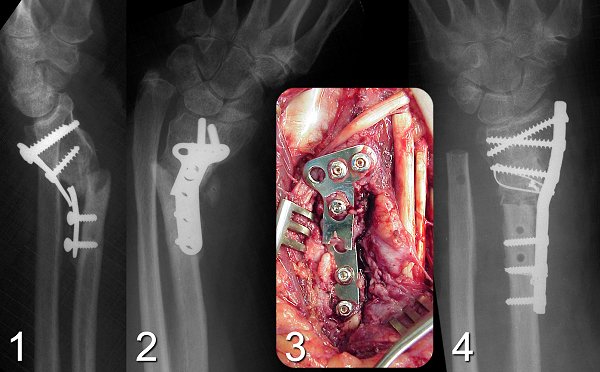

Figure Legend: Distal radius nonunions

are uncommon, but usually symptomatic due to progress of angulation and

symptoms from distal radial ulnar joint disruption. This patient

developed progressive angulation and hardware failure following dorsal

plating of a Galeazzi type metaphyseal distal radius fracture dislocation

(1, 2). The original surgeon should have used a more sturdy plate

and should have captured more cortices proximally. At exploration,

soft tissue interposition was found in the fracture line, and the extensor

pollicis longus tendon was on its way to an attritional rupture, positioned

behind the plate (3). The fracture was reduced, stabilized with a

3.5mm plate and cerclage, and the distal ulna was used as bone graft (4).